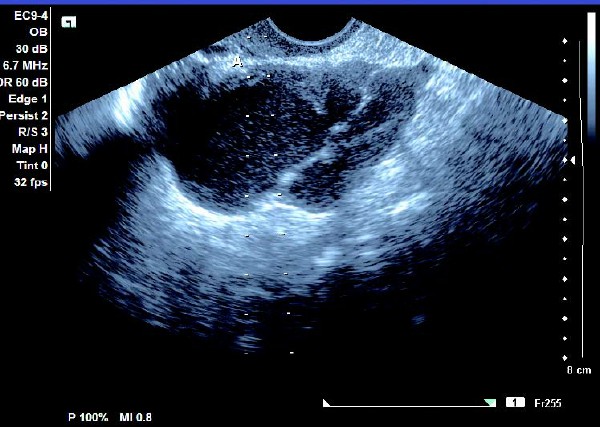

1.单纯囊肿型

(1)单侧或双侧卵巢内呈现椭圆形或圆形无回声暗区,其内充满弱回声光点,囊肿直径一般为5~6 cm,大于10 cm 的较少见。

(2)壁较厚,囊内充满细小均匀点状回声,后方回声增强。

(3)常与周围组织有粘连,边界清晰。

患者,女,35岁。每次月经量少,痛经,近来行经期延长、疼痛加重来院诊治。超声报告显示子宫前倾位,子宫体大小为:5.9cm×5.1cm×4.8cm,形态规则,边界清晰,宫避回声匀称,宫腔线居中,内膜厚度0.6cm,宫内未见异常回声。右侧卵巢内可见大小约5.2 cm×4.9cm的无回声区暗区,壁厚,内壁欠光滑,内见密集细光点,边界清晰。CDFI探测囊壁及囊腔内无血流信号。

超声提示:右侧卵巢巧克力囊肿